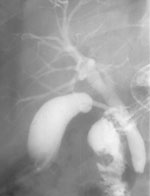

4. Больной З., 47 лет, страдающий хроническим панкреатитом, поступил в хирургию

с наличием гнойного свища на заднебоковой поверхности брюшной стенки. В анамнезе

у больного произведено оперативное вмешательство, заключающееся в наложении

цистогастроанастомоза (анастомоз между кистой поджелудочной железы и желудком),

после которого больной чувствовал себя хорошо. Однако наличие свища позволило

предположить облитерацию анастомоза. Одновременное исследование желудка и введение

контраста в свищевой ход подтвердило это предположение (Рис. 4).

Рис. 4. Выполнена фистулография (контраст в ретрогастральном

пространстве) и контрастирован желудок. Ранее наложенный анастомоз

между кистой поджелудочной железы и желудком не контрастируется.